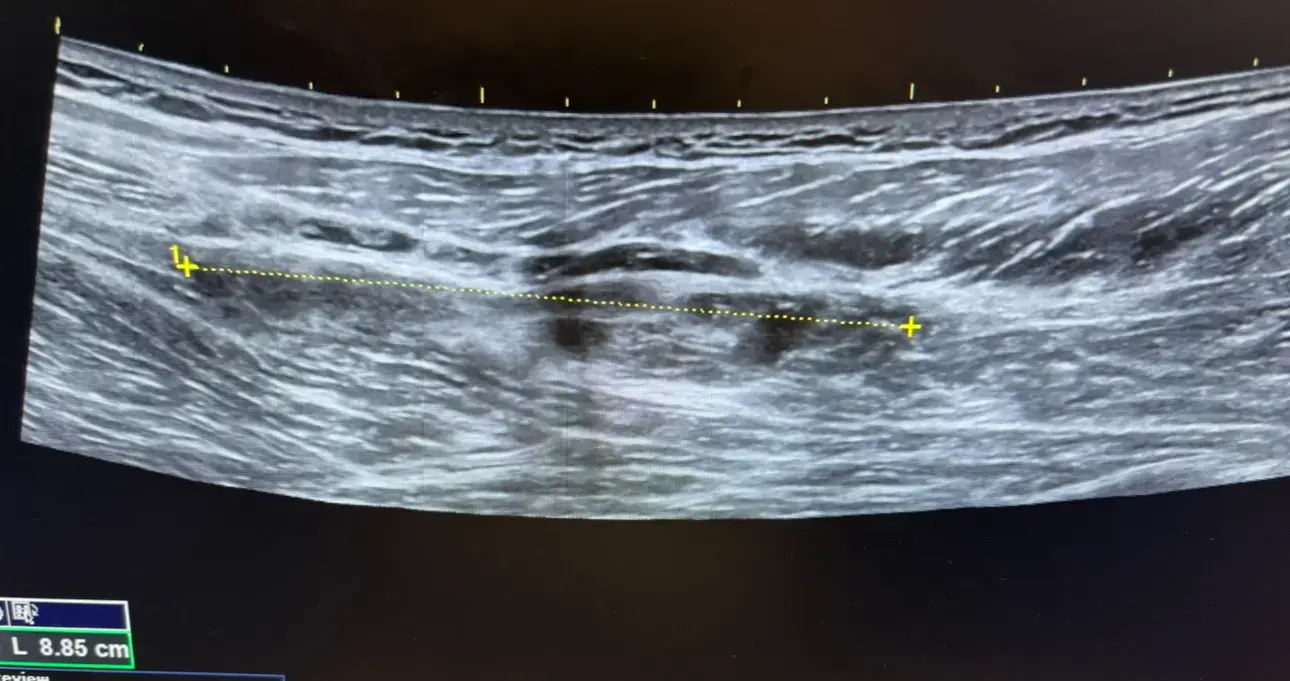

Boston Sports & Biologics is a multidisciplinary orthopedic practice that focuses on non‑surgical, minimally invasive treatment of acute and chronic musculoskeletal injuries. The clinic leverages high‑resolution diagnostic musculoskeletal ultrasound to accurately diagnose tendon, ligament, nerve, and joint pathology, allowing for precise, ultrasound‑guided therapeutic interventions. Their approach emphasizes personalized care plans that target the underlying cause of pain rather than merely addressing symptoms, with the goal of restoring function while avoiding traditional orthopedic surgery. The practice offers a comprehensive suite of regenerative and orthobiologic therapies, including platelet‑rich plasma, bone‑marrow concentrate, micro‑fragmented adipose tissue (Lipogems), stem‑cell‑derived treatments, and hyaluronic‑acid viscosupplementation. These biologic options are complemented by percutaneous tenotomy (Tenex), nerve hydrodissection, trigger‑point injections, shockwave therapy, and prolotherapy, all performed under ultrasound guidance to maximize accuracy and safety. The team also provides ultrasound‑guided carpal‑tunnel and trigger‑finger releases, as well as peripheral joint and soft‑tissue injections. Founders Dr. Walter Sussman and Dr. Erek Latzka are dual board‑certified physicians in Physical Medicine & Rehabilitation and Sports Medicine, with extensive clinical, research, and teaching experience in ultrasound‑guided procedures and regenerative medicine. Their combined expertise, supported by academic affiliations with Tufts University and the University of New England, positions the practice as a leader in innovative musculoskeletal care throughout New England.